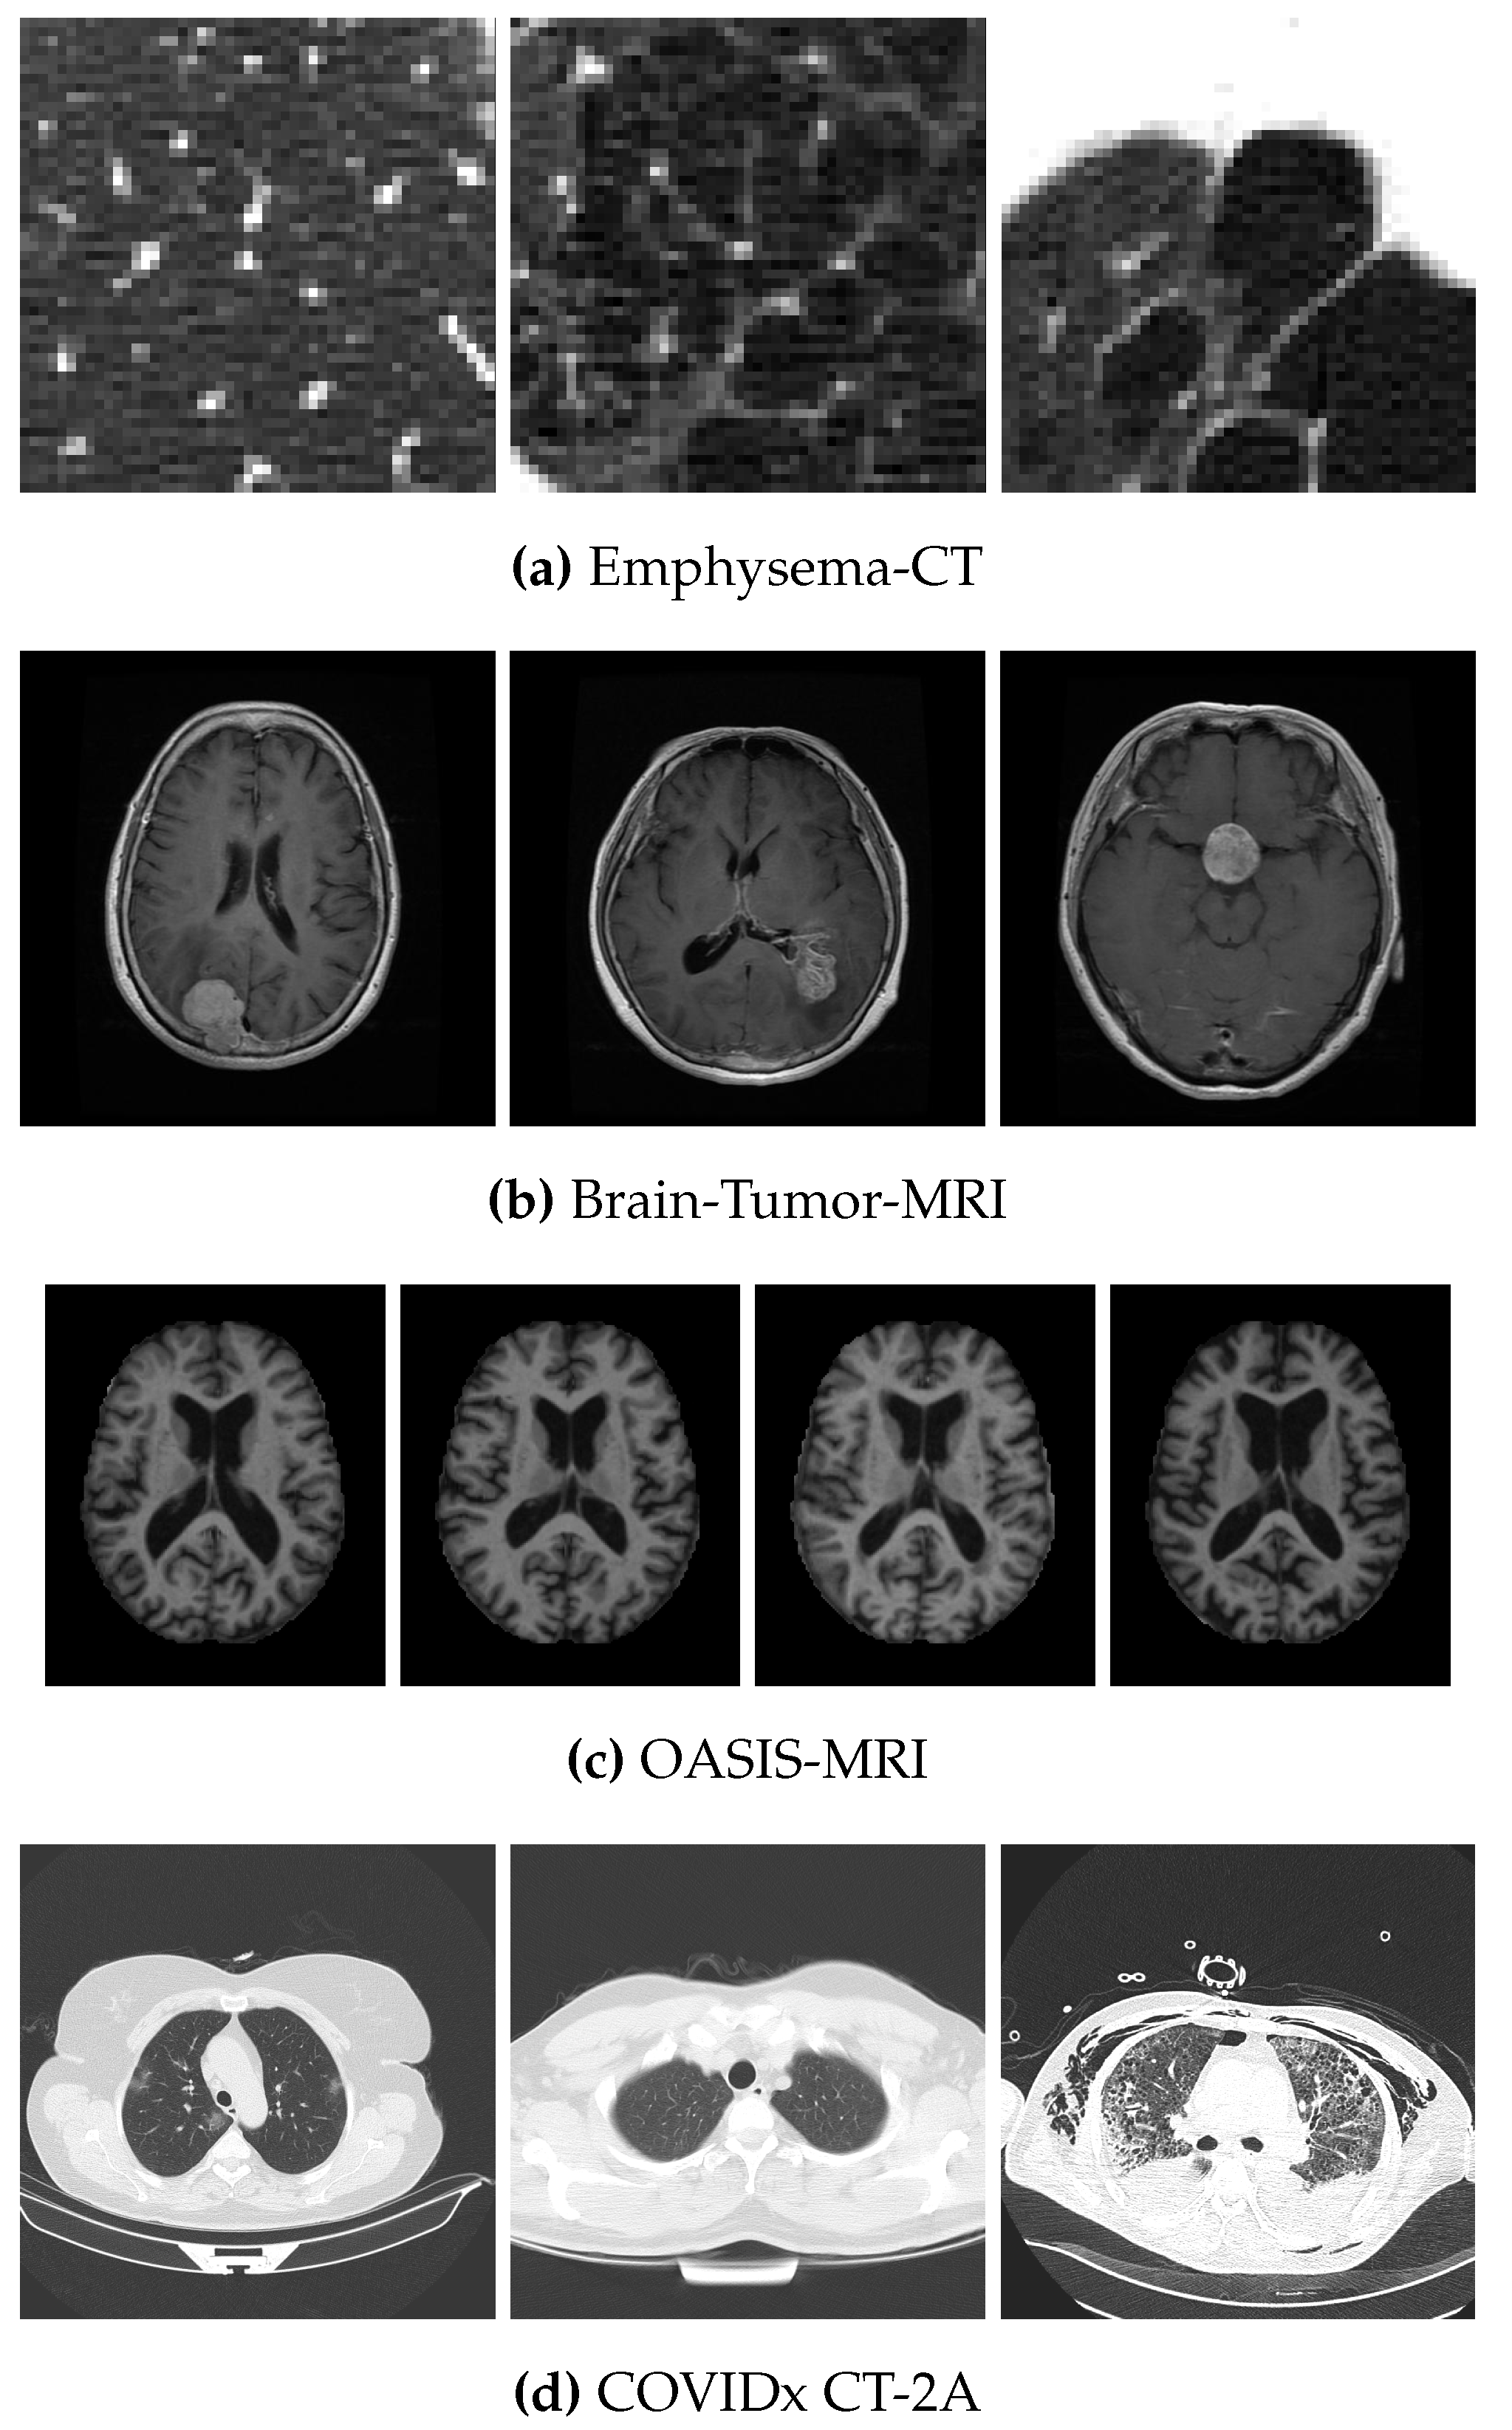

4.1. Data Sets

- Sørensen, L.; Shaker, S.B.; de Bruijne, M. Quantitative Analysis of Pulmonary Emphysema Using Local Binary Patterns. IEEE Trans. Med Imaging 2010, 29, 559–569. [Google Scholar] [CrossRef]

| Data Set | No. of Images | Size | Classes | No. of Images per Class |

| Emphysema-CT | 168 | 3 | 59–50–59 | |